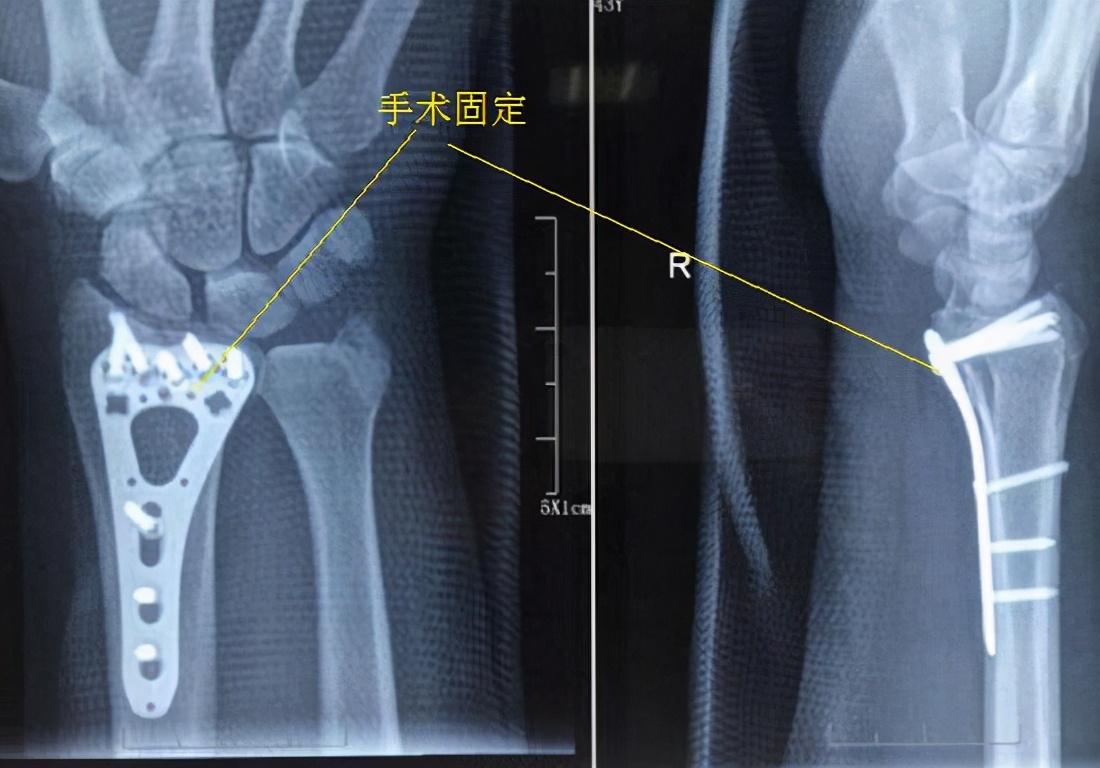

0-6周 1、将首要目标确定为防止肿胀、僵硬。2、稳定型的、非手术治疗的骨折,起初应使用长臂方糖夹式夹板固定肘、腕关节,进行积极的肩关节和手指关节活动练习,在3-4周后当骨折达到一定愈合度时,则要更换只固定腕关节的短臂夹板,并同时进行肘关节的活动练习。如果是牢靠的手术内固定,术后即可开始肩关节和手指关节的活动练习,在拆线后同时进行肘关节的活动练习,并允许腕关节活动(仍要使用短臂夹板在夜间和其他时间对肘关节进行必要固定)。3、尝试进行功能性活动,例如,尝试拿比较轻的物品,抓握东西等。针对稳定的内固定、稳定型骨折、或者骨折愈合到一定程度时,可进行穿衣、吃饭、写字、上厕所等日常活动。4、如果是稳定的内固定,在拆线后就可尝试进行前臂旋前和旋后动作;针对非手术治疗而言,稳定型骨折、或达到一定愈合度的骨折,应尽早实施前臂旋前和旋后练习。5、手术治疗者,采用按摩、硅胶贴等方式处理瘢痕,避免切口区的粘连和挛缩。